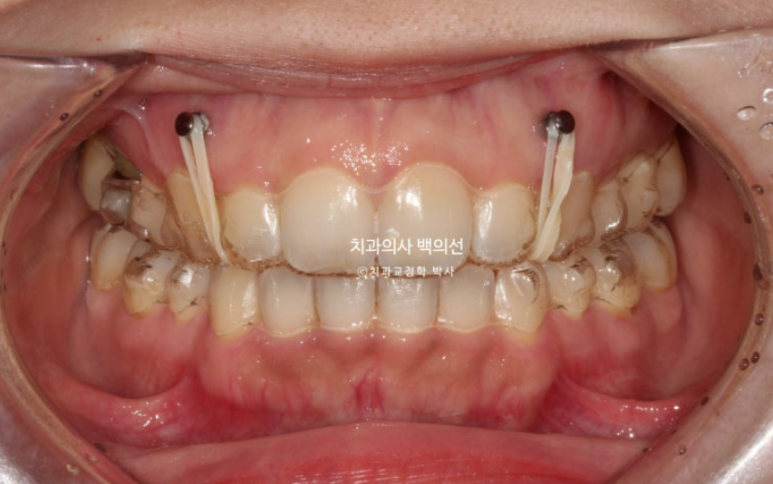

24.09

단 과개교합이 심해 투명장치만으로는 해결이 어려워 앞니쪽에 교정용 나사인 미니스크류를 심고 고무줄을 같이 사용했습니다.

24년 4월부터 9월까지 6개월간 14개 장치를 모두 낀 후 모습입니다.

과개교합은 개선이 되어 아래앞니가 보입니다.

발치공간도 대부분 없어졌으나 미세한 공간이 여전히 남아있습니다.

추가장치 한세트를 더 써서 과개교합을 더 개선하고 발치공간을 타이트하게 마무리짓기로 하고 재제작에 들어갑니다.